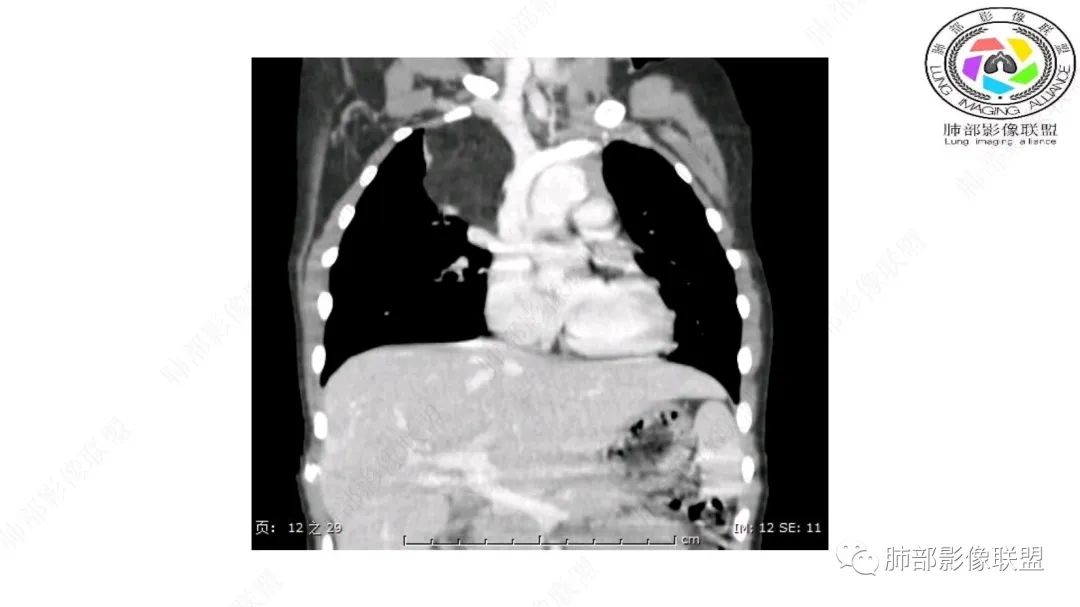

右上纵隔混杂密度肿块,边缘光整,与纵隔分界清,其内多发脂肪密度,增强无明显强化,其内血管穿行,考虑纵隔脂肪母细胞瘤,鉴别畸胎瘤,脂肪肉瘤。

右纵隔团状,密度不均,脂肪密度为主,内可见腺体样组织,类似乳腺,病灶边缘有分叶,与胸腺关系密切,增强后血管穿行。考虑胸腺脂肪瘤(不典型垂乳征),鉴别畸胎瘤。

三岁小儿,右侧纵隔巨大脂肪密度肿块,肺动脉穿行其中,密度欠均匀,未见明确实性成分,纵隔脂肪母细胞瘤,冬眠瘤鉴别纵隔脂肪增多症(多弥漫对称)。

患儿3岁 咳嗽检查发现纵隔占位。右肺上叶受压表现,占位以脂肪组织密度为主,似见分隔,首先考虑为脂肪母细胞瘤,鉴别脂肪瘤,畸胎瘤。

幼儿,右上纵膈团块,脂肪密度,内见分隔,增强病灶内见血管穿行,结合患者年龄,考虑脂肪母细胞瘤,鉴别脂肪瘤。

纵隔畸胎瘤,右前上纵隔团状脂肪密度?粘液样密度为主病变,病灶软边缘有分叶,内可见分隔,增强后血管穿行。3岁。考虑纵隔脂肪母细胞瘤,鉴别畸胎瘤。

病灶属于交界区,主体位于肺内,占位效应明显,前方突入胸壁,胸腺受压变形,胸膜显示欠清楚;病灶包绕上叶肺动脉;似乎有体动脉供血。符合肺内的点:包绕上叶肺动脉分支;符合纵隔的点:前方似乎突入胸壁,与胸腺关系比较密切,但是与上腔静脉的关系提示病灶不支持纵隔来源,前纵隔的常规会将上腔静脉受压后移、外移,这是不符合的。

2.肺动脉穿行也许是肺内来源最重要支持点!

脂肪母细胞瘤由成熟程度不同的脂肪组织、纤维间隔、黏液基质、小血管丛等间质成分组成,以脂肪组织与黏液样基质为主,其影像学表现取决于上述组织成分。典型的CT和MRI表现为:前后纵隔均可发生,常见于前纵隔;肿块大小不一,直径多在3cm~7cm,密度均匀,CT值呈水样或脂肪密度,脂肪组织密度或信号为主的肿块,其内密度或信号不均匀,可见粗细不一的分隔影,且有结节、片状影,后者可呈轻中度强化;结节状肿瘤包膜完整;弥漫性者包膜不明显,常呈浸润性生长;周围结构为受压和推移改变,可有少量胸腔积液,淋巴结无增大。